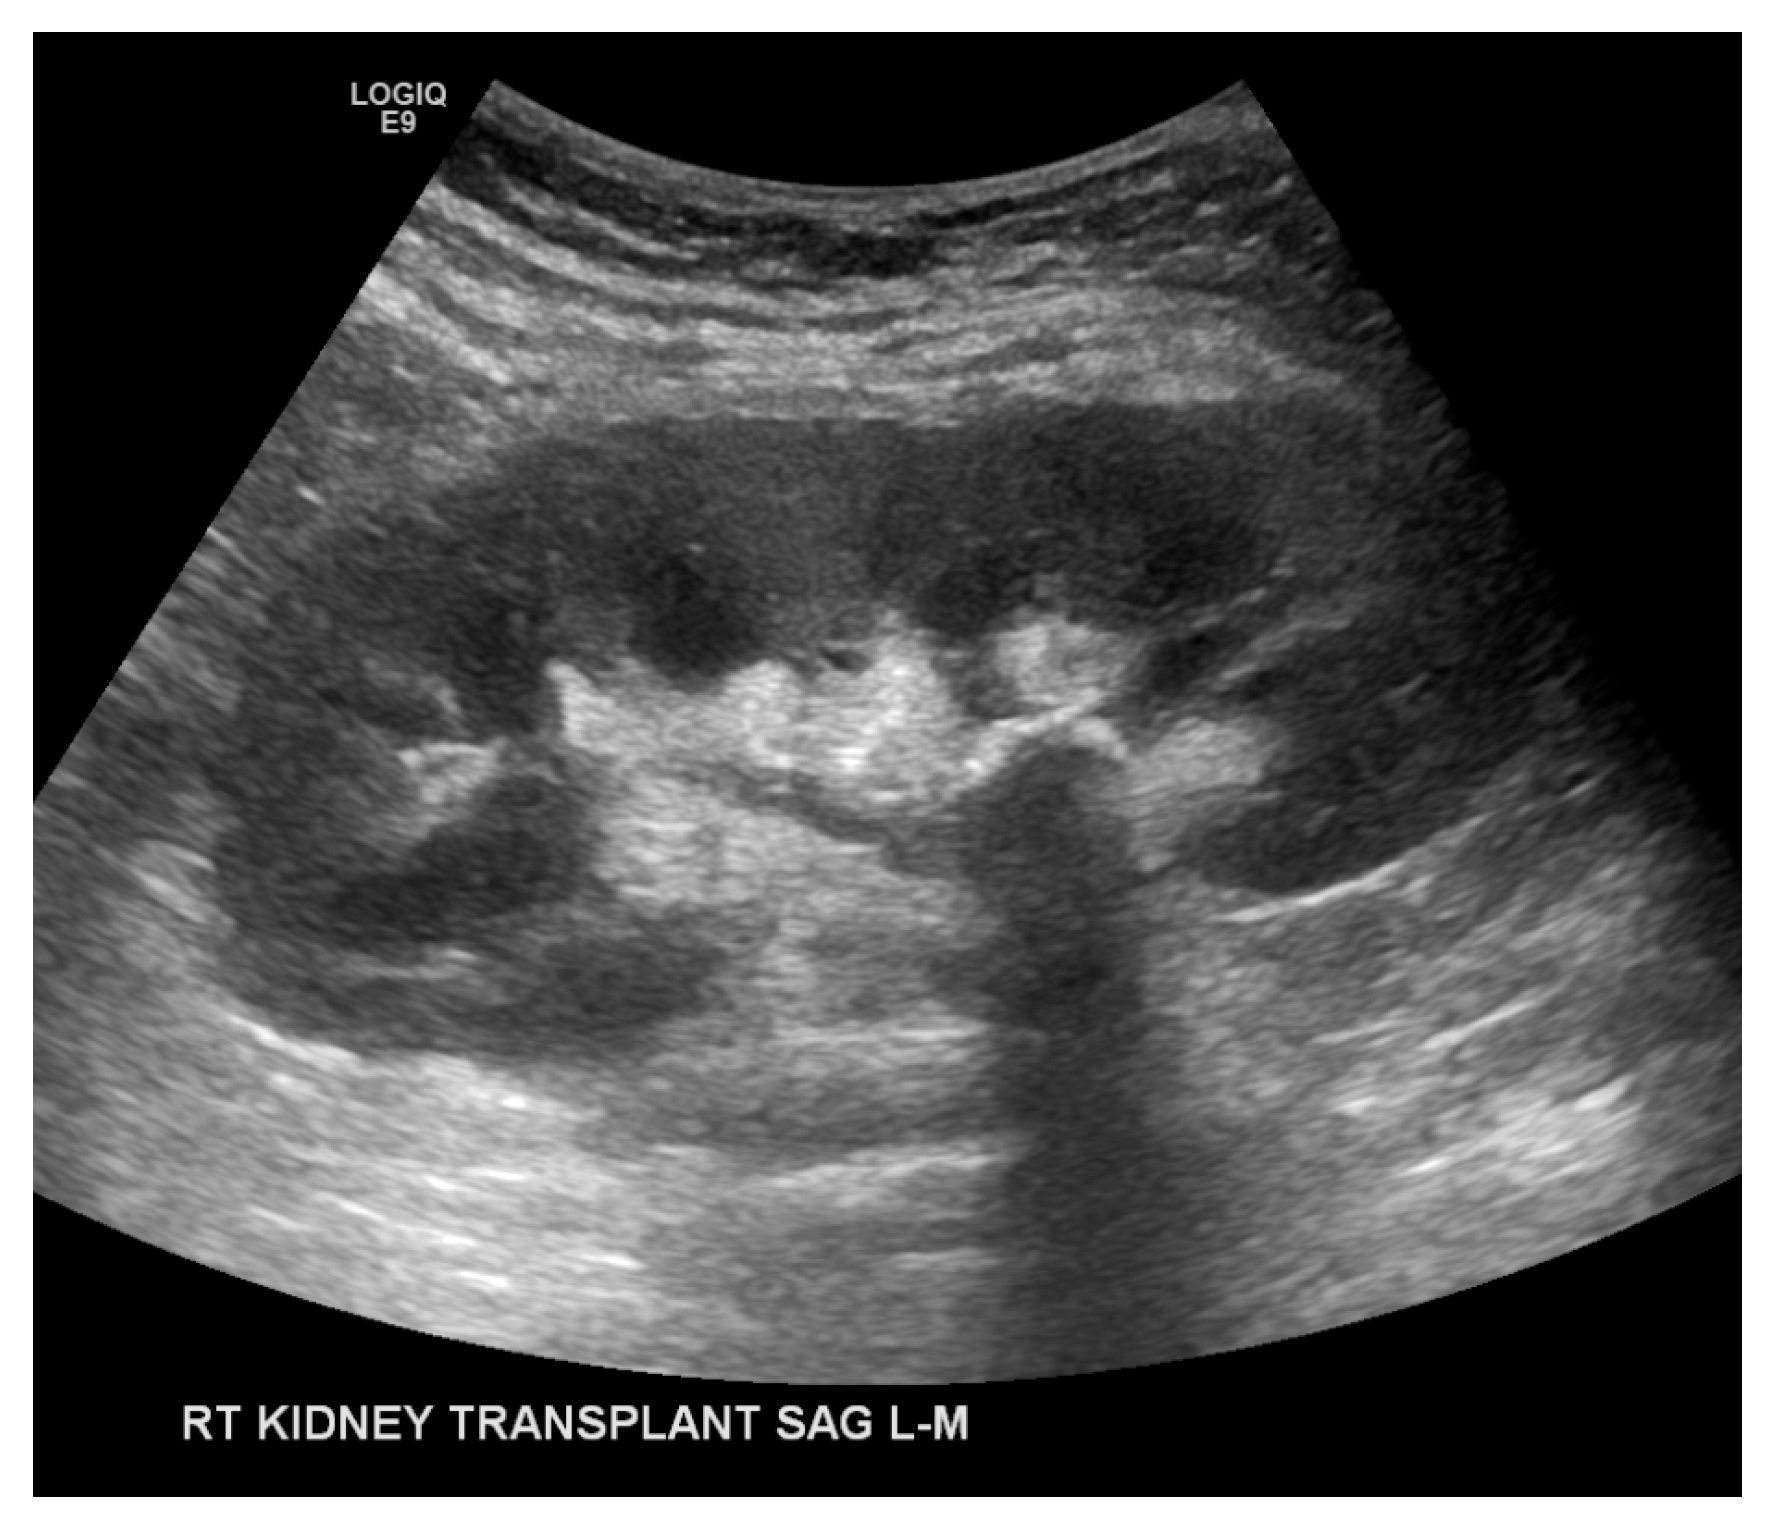

The CT scan without contrast was repeated on post-operative day 6, which demonstrated dense dilatation of the renal collecting system and appropriate positioning of the ureteral stent (Figure 2). His urine output subsequently decreased—producing approximately 150 mL in 24 h. A repeat ultrasound demonstrated a dilated renal pelvicalyceal system containing echogenic debris (Figure 3), so the decision was made to remove the ureteral stent due to likely occlusion on post-operative day 8. Upon manipulation and removal of the stent, a large amount of old blood sediment immediately drained from the ureteral orifice. Urine output improved significantly after stent removal with resolution of hematuria. On post-operative day 10, renal function continued to improve: creatinine 4.3 mg/dL and eGFR 15 mL/min/1.73 m2. He was discharged and scheduled for close outpatient follow-up.

The patient’s renal function remained stable over the next year (creatinine 1.0–1.3 mg/dL, eGFR 53–78 mL/min/1.73 m2). However, the patient experienced three urinary tract infections during this time: the first was Escherichia coli and the latter two Klebsiella pneumoniae. An ultrasound at nearly 1-year post-transplant demonstrated an echogenic structure in the renal pelvis concerning for a renal calculus (Figure 4). A follow-up CT scan demonstrated an irregular soft-tissue density with rim calcification at the ureteropelvic junction measuring 5 × 3.5 centimeters and minimal transplant kidney pelvicaliectasis (Figure 5). Ureteroscopy was attempted but unsuccessful due to difficulty cannulating the ureteral orifice at the bladder dome.

Figure 3. Transplant kidney ultrasound demonstrated the proximal end of the ureteral stent within the renal pelvis (A) and persistently dilated renal pelvicalyceal system containing echogenic debris (A,B).

Figure 4. Post-transplantation 1-year follow-up kidney ultrasound demonstrated an echogenic structure in the renal pelvis with posterior shadowing concerning for a renal calculus.